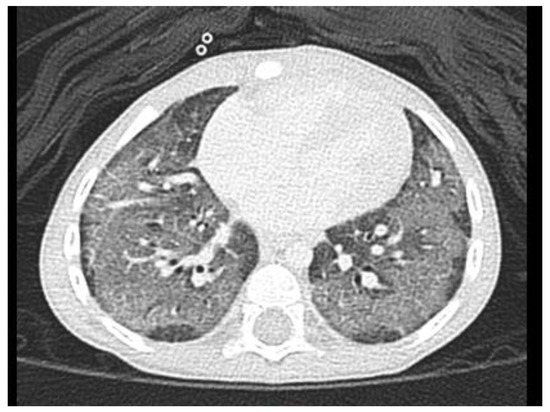

A series of examinations was performed to establish the final diagnosis. Her blood gas pH value was within the normal range, without carbon dioxide retention or metabolic acidosis. A chest x-ray showed diffusely increased density of both lungs (Figure 1A). Lung echo suggested pulmonary edema (Figure 2), and furosemide was administered. Chest

Figure 1. (A) Chest x-ray on admission showed diffuse increased interstitial density of both lungs. (B) Chest x-ray after treatment revealed no radiologic evidence of active cardiopulmonary disease.

Computed tomography (Figure 3) showed suspected interstitial pneumonia in both lungs with a crazy-paving appearance. Bronchoscopy was performed, and no evidence of bleeding or micro-aspiration was noted in bronchoalveolar lavage (BAL) with negative culture. Pulmonary hypertension with an estimated systolic pulmonary artery pressure of 45 mmHg was revealed on echocardiography, and sildenafil treatment (1 mg/kg/day, 3 doses/day) was started. Based on the above examinations, children’s interstitial lung disease (chILD)-induced secondary pulmonary hypertension was assessed, and steroid (Betamethasone 0.04 mg/kg/day, 3 times per day) and azithromycin (10 mg/kg/day, 3 days/week) were given as anti-inflammatories. She was then discharged in relatively stable condition, with medication as described above and home care oxygen supply.

After establishing the final diagnosis of SP-C deficiency, we started the treatment with hydroxychloroquine (10 mg/kg/day in two divided doses). We discontinued azithromycin, and gradually tapered down steroid dosage within one month. She was then regularly followed up with through the outpatient department. After two months of treatment with hydroxychloroquine, her condition had markedly improved and her oxygen demand decreased gradually. Follow-up echocardiography was normal, without pulmonary hypertension; therefore, we discontinued sildenafil use. She took hydroxychloroquine for 21 months, and room air was well tolerated without cyanosis or exertional dyspnea. A chest X-ray revealed normal findings (Figure 1B), although lung function tests performed after halting medication still showed restrictive pulmonary disease. She was well fed after respiration improved. Her height (28th percentile) and weight (41st percentile) also caught up to the normal range. Two years after withdrawing the medication, the patient was four years old and she remained well, with no clinical or radiological signs of relapse.